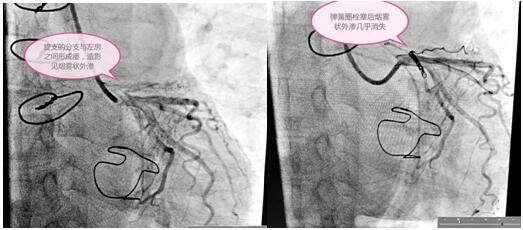

定于3月3日进行冠状动脉瘘弹簧圈栓塞手术,术前手术团队为患者细心指导,消除患者紧张情绪,穿着手术衣,带着一次性手术帽和普通外科口罩,做好防护。吴栋梁院长和高胜利主任手术团队为患者精心进行了手术,要将大小合适的弹簧圈放在血管远端狭窄处封住瘘口,患者冠脉及分支血管比较迂曲,会导致手术过程比较复杂,耗时长,这些在手术方案里均考虑到。初始常规使用的导丝通过困难,后来根据患者血管走形我们又选择了微导管和特殊的导丝,导管室很安静,能听到的只有时钟的滴答声和我的心跳声,调整了手术器械后弹簧圈很快送到位并释放,手术终于圆满结束,比我们预计的手术时间提前了半小时。

术前与术后